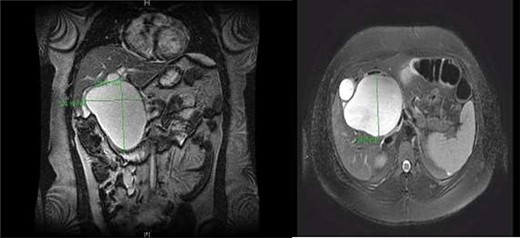

(Left) intra-operative CC and replace right hepatic artery. (Right) decompressed gallbladder (GB) and decompressed CC.

A right upper quadrant abdominal ultrasound was obtained which showed that the gallbladder wall was 3 mm, an obscured common bile duct (CBD), and a cystic lesion communicating with the CBD and a large gallbladder cyst (Fig. 2). A contrast MRI with magnetic resonance cholangiopancreatography (MRCP) of the abdomen revealed marked fusiform dilatation of the extrahepatic CBD measuring 8.8 cm anterior–posterior x 10.9 cm transverse x 12.7 cm craniocaudally, mild-to-moderate central intrahepatic bile duct dilatation and posterior displacement of the patent main portal vein due to associated mass effect (Fig. 3). Based on the image findings the diagnosis of a CC was made. The type, however, could not be definitively diagnosed as the cyst could be a large type I CC with resultant upstream intrahepatic ductal dilatation versus a type IVa CC with associated mild to moderate central intrahepatic biliary ductal dilatation. Upon review of the images, labs, assessment of the patient, she was scheduled for resection of the extra hepatic bile duct and choledochal cyst with planned Roux en y hepaticojejunostomy. Intraoperatively, she was found to have a massive 20 cm type I choledochal cyst (Fig. 4).